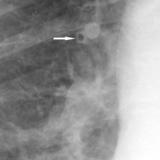

APE 1

Date: 11/05/2005

Views: 4196